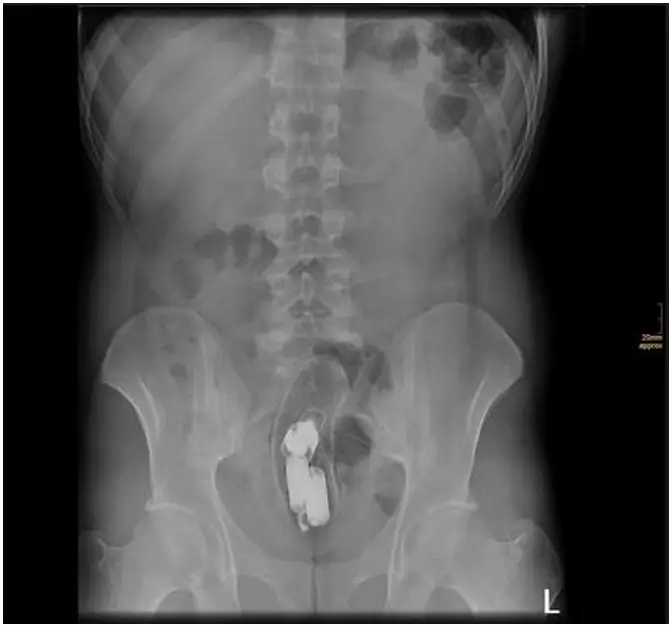

sesamoid-injuries Sesamoid Injuries & Disorders The sesamoid bones (small bones beneath the big toe joint) can develop painful conditions due to acute trauma or chronic stress. Acute Sesamoid Injuries (Turf Toe & Fractures) Chronic Sesamoid Conditions Includes stress fractures, avascular necrosis (bone death), and sesamoiditis (inflammation)—often overlapping in symptoms. Lesser Toe Deformities: Hammer, Mallet & Claw Toes These deformities […]